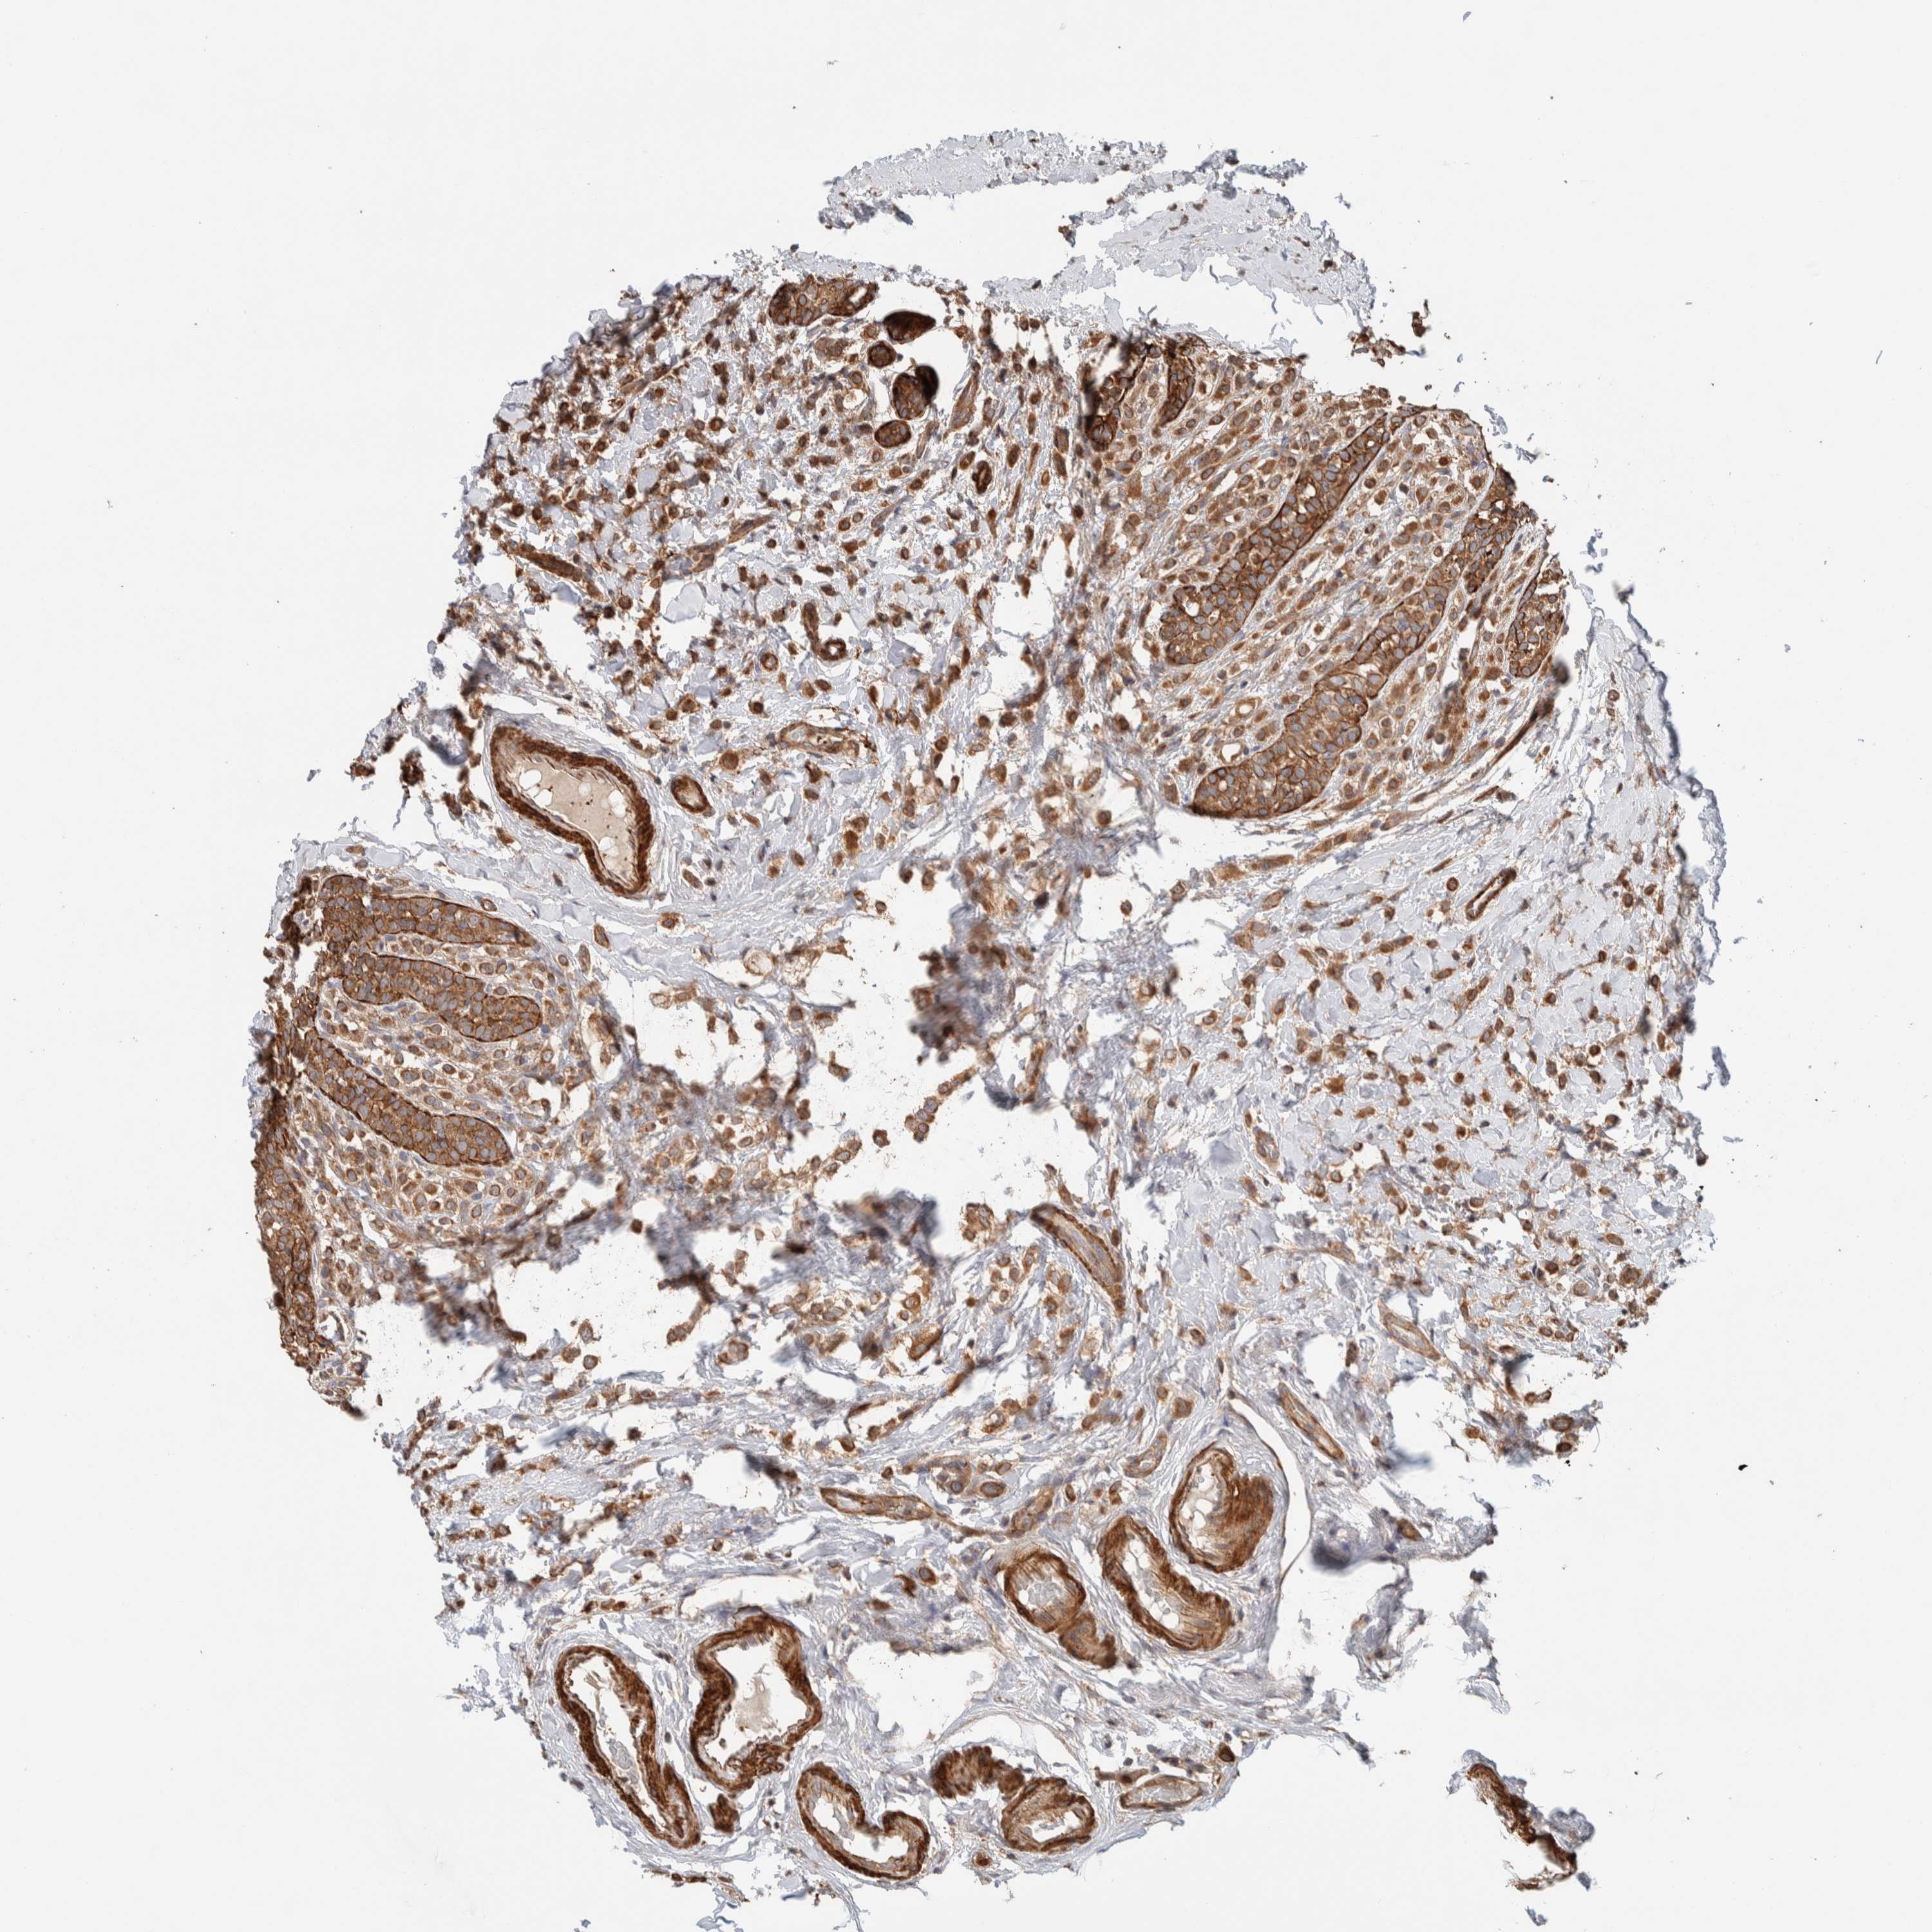

CANCER BREAST CANCER Show tissue menu

BRCA TCGA BRCA VALIDATION PROTEIN EXPRESSION